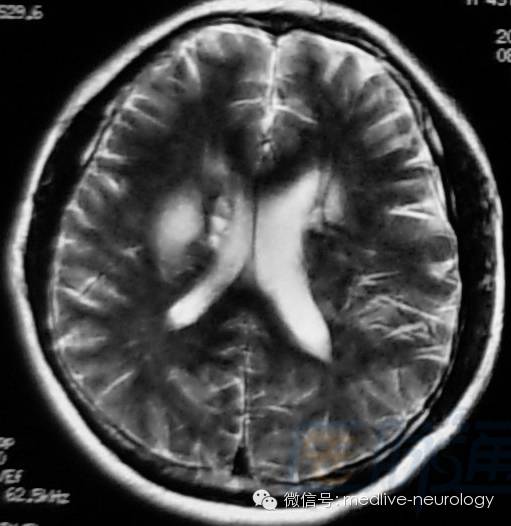

然后解决第三个问题,轻松一下,图来啦,让我们巩固一下今天学习的成果,均为先T1,后T2。

急性期(1-3d):右枕叶